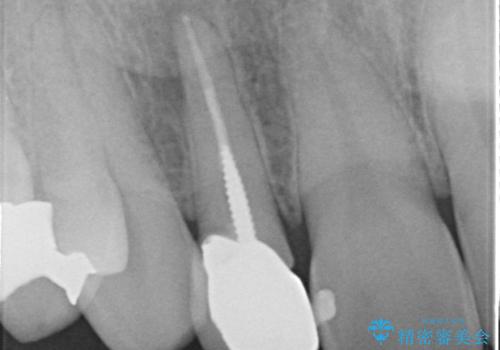

- 金属を使っていない被せ物に替えたいといらっしゃった方の症例です。

再根管治療終了後、オールセラミッククラウンによる補綴を行いました。

- オールセラミッククラウン(スペシャル)…¥130,000、仮歯…¥10,000、ファイバーコア…¥20,000、精密根管治療費別途費用は治療当時の料金となります